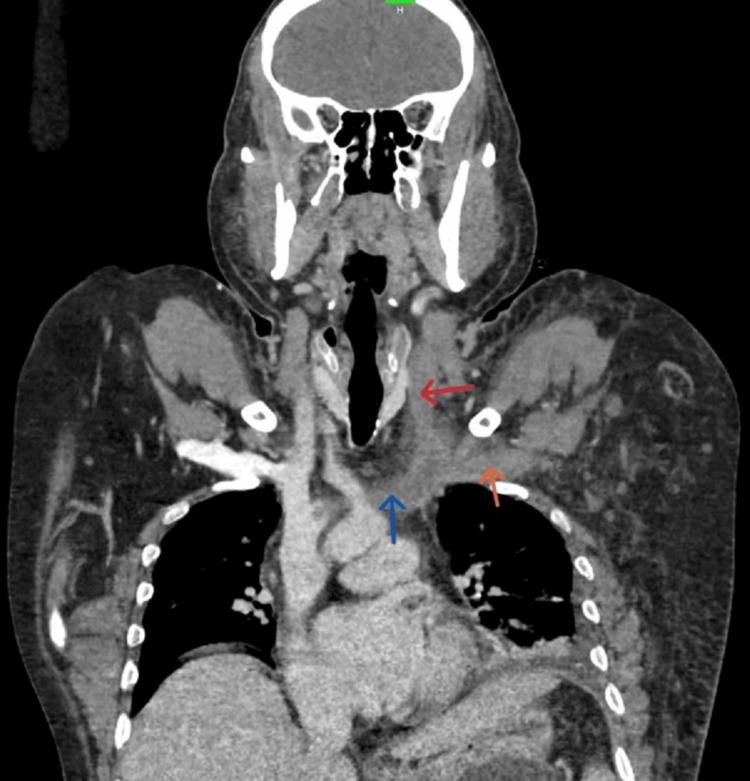

Acute pancreatitis (AP) is an inflammatory condition with varied clinical presentations. Local complications include peripancreatic fluid collection, acute necrotic collection, walled-off necrosis, and pancreatic pseudocyst, but vascular complications like pseudoaneurysm and venous thrombosis are also reported. Patients often experience splanchnic venous thrombosis, which can affect the splenic vein, portal vein, and superior mesenteric vein individually or in combination. Rarely, extra-splanchnic venous thrombosis, including renal vein, superior vena cava, and inferior vena cava thrombosis, has been reported in cases of chronic pancreatitis. The formation of a venous thrombus in acute pancreatitis is multifaceted, with pancreatic inflammation and the immune response mounted by the patient playing a significant role. There is a dearth of medical literature regarding extra-splanchnic venous thrombosis and the use of therapeutic anticoagulation in the successful treatment of the above-mentioned complication. This case report highlights the rare complications that can be seen in cases of acute pancreatitis.

急性胰腺炎(AP)是一种临床表现多样的炎症性疾病。局部并发症包括胰周液体积聚、急性坏死性积聚、包裹性坏死和胰腺假性囊肿,但也有报道称存在诸如假性动脉瘤和静脉血栓形成等血管并发症。患者常发生内脏静脉血栓形成,可单独或联合累及脾静脉、门静脉和肠系膜上静脉。在慢性胰腺炎病例中,罕见报道有包括肾静脉、上腔静脉和下腔静脉血栓形成在内的内脏外静脉血栓形成。急性胰腺炎中静脉血栓的形成是多方面的,胰腺炎症和患者的免疫反应起了重要作用。关于内脏外静脉血栓形成以及使用治疗性抗凝剂成功治疗上述并发症的医学文献较少。本病例报告突出了急性胰腺炎病例中可能出现的罕见并发症。